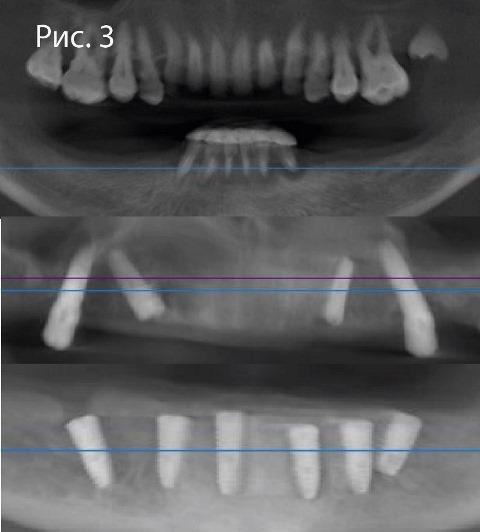

До

После

До и после